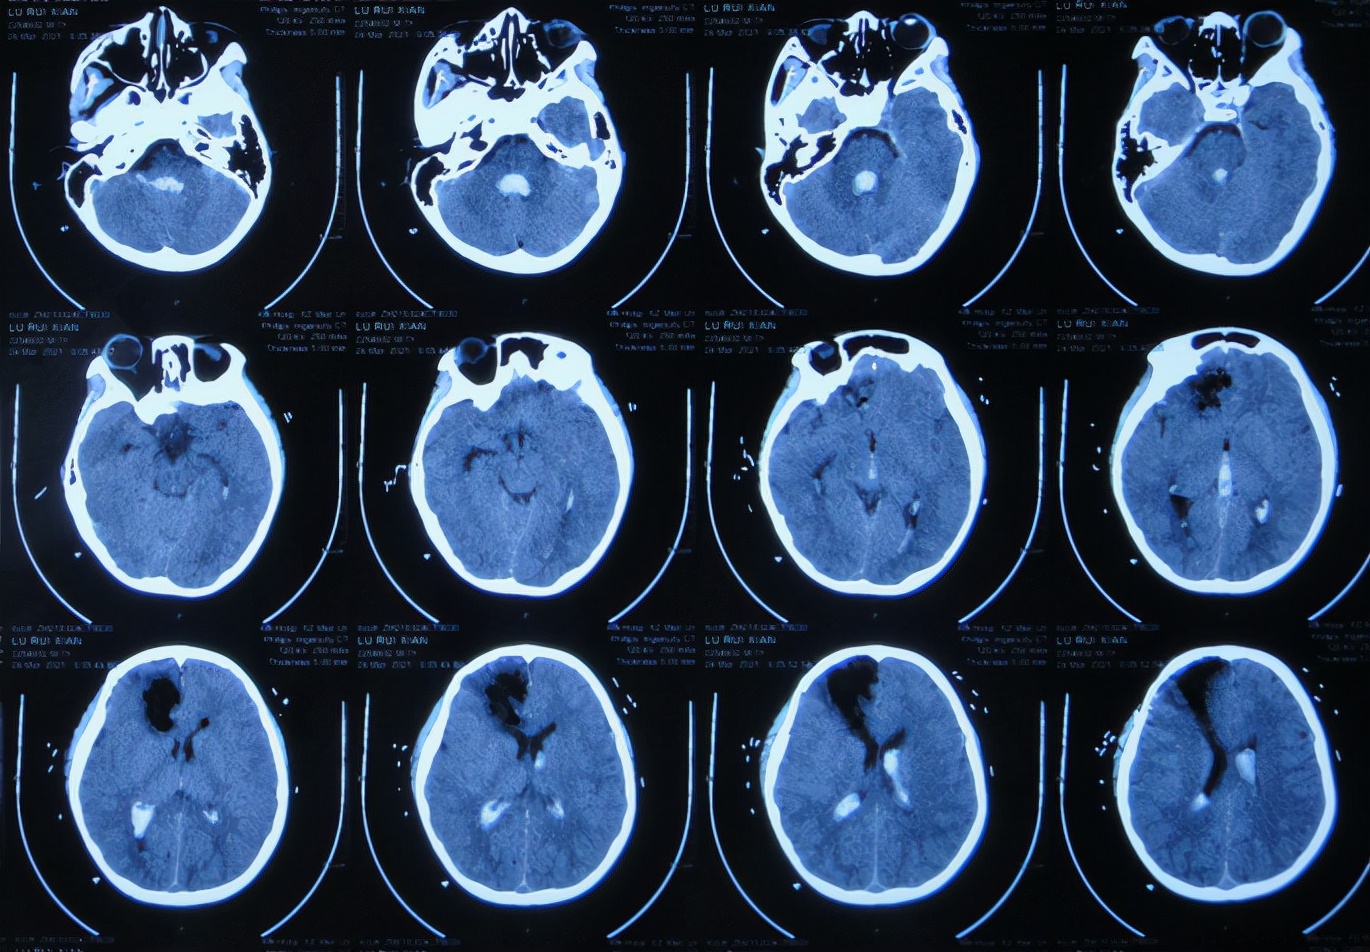

患者2021年3月23日早起突发头痛,意识不清,急送至江苏省徐州市睢宁县某医院,查脑CT示脑出血( 图-1 );既往史有癫痫病史。

图-1: 2021年3月23日脑CT